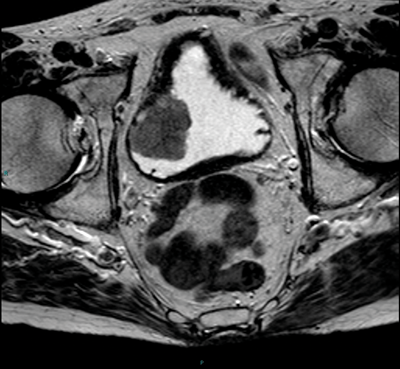

Figure 4. Early contrast enhanced images of the same patient as Figures 2

and 3 show avid enhancement of the internal half of the bladder wall.

If the tumour is seen to enhance, close evaluation is needed to assess if this is full thickness or less than half the thickness of the wall in order to provide radiological staging (Figure 4). The distal ureter may also be seen to enhance if the tumour is close to the ureteric orifice (Figure 5).